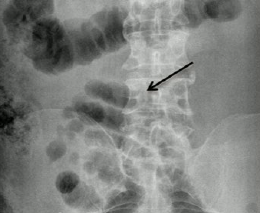

Q

Pathology?

small bowel obstruction

dilated loops of small bowel, paucity of bowel gas distally

normal for comparison